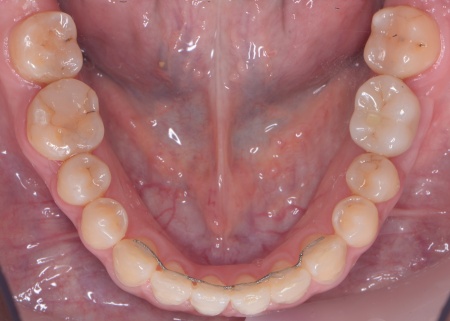

| カウンセリング | 拝見したところ、右上と左下の奥歯に強い痛みが出ていました。 レントゲンで確認した結果、どちらも歯の根が割れていることが判明しました。 歯の根が割れたまま放置すると噛むときの痛みが続くだけでなく、炎症が広がって周囲の歯や骨にまで影響を及ぼすおそれがあります。 また、上下の歯を噛み合わせた際に前歯が噛み合わず隙間ができる開咬(かいこう)と呼ばれる噛み合わせも見られました。 以上のことから、抜歯後に歯を補う治療と噛み合わせを改善するための治療が必要と診断しました。 |

患者様は「健康な歯をできるだけ守りたい」との理由から、③のインプラント治療を希望されました。 まず、右上と左下の奥歯を抜歯しました。 矯正がある程度進んだ段階で、右上と左下のインプラント手術を実施しました。 インプラント手術後は矯正治療の仕上げを行い、装置を外しています。 治療終了後、下前歯の間に見られる三角形のすき間(ブラックトライアングル)が気になるとのご相談がありました。 |